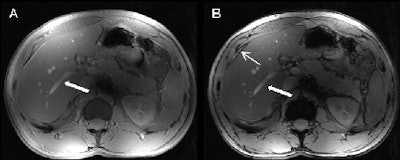

Their analysis found that of the noncontrast-enhanced MR images, 2D FLASH imaging had the highest mean scores for overall image quality (mean score of 4.52), for vessel delineation (mean score of 4.22), and for phase imaging (mean score of 4.40).

Dynamic 3D FLASH imaging yielded good contrast enhancement of the liver and improved visualization of the liver's arteries and veins, while the portal veins were well defined in nonenhanced and all phases of dynamic imaging.

The study also found that postcontrast 2D FLASH improved conspicuity of the peripheral liver vasculature, but there was no statistically significant difference when compared to noncontrast-enhanced 2D FLASH MRI.

In addition, the authors wrote, 7-tesla MRI created a "very good depiction of the liver vasculature with only minor improvement of conspicuity after the application of intravenous gadolinium administration."